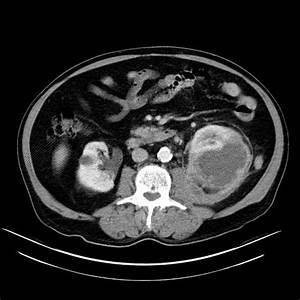

Quando solicitar TC na pielonefrite?

Dúvida diagnóstica, abscesso ou obstrução, falha terapêutica